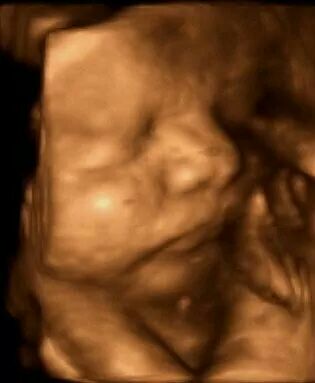

Having a baby

Dr Emma Buckland is an experienced obstetrician who enjoys managing both high and low risk pregnancies. Her main focus is the health of mother and baby at all times, but having said that, she is happy to allow nature to take it’s course during the birth process and encourages active labour and vaginal birth. She will support women in their decision to have a vaginal birth after cesarean, a vaginal breech birth, or vaginal birth of twins. She also offers External Cephalic Version (turning a breech baby in the womb). Sometimes a caesarian birth, an epidural or an assisted birth is needed and this is a decision made after discussion with the couple. As Emma delivers less than 10 babies per month in her private practice she has the time and energy to get to know each couple and to work with each mother to provide individualised care.